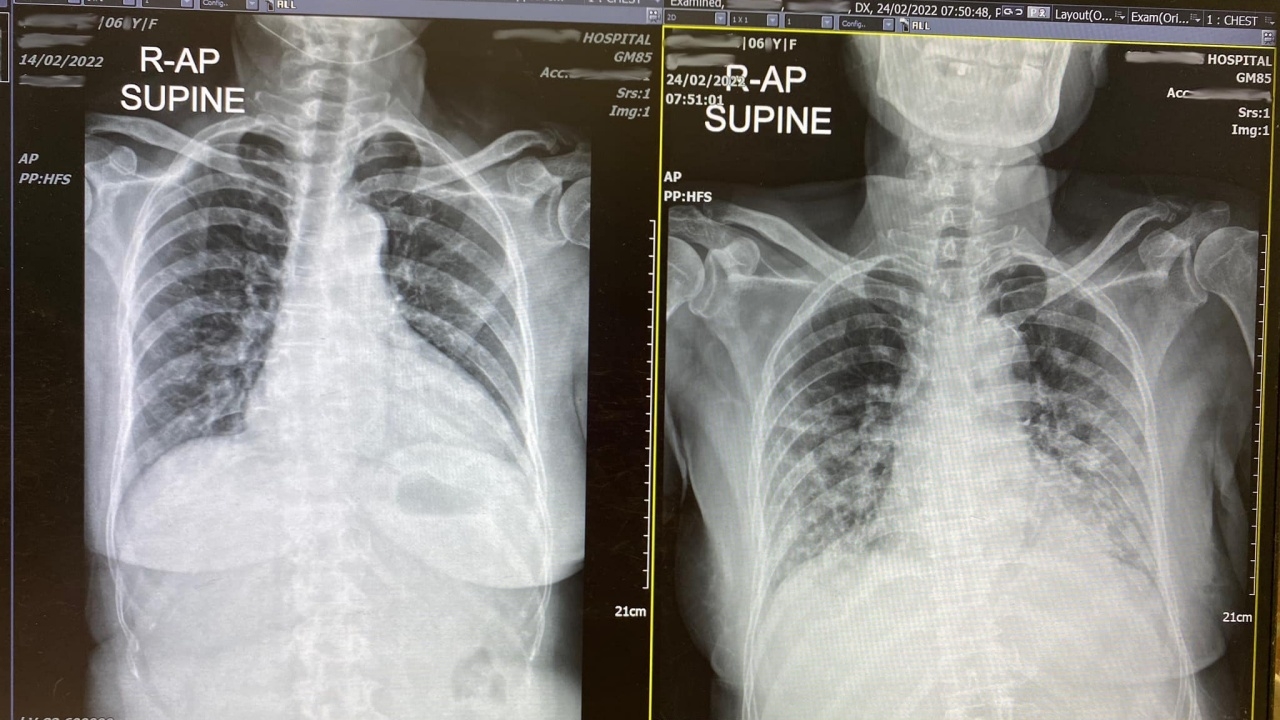

สุดท้ายวันที่ 10 ไม่ได้กลับบ้านเหมือนเคสอื่นๆ ที่อาการเบา แต่อาการแย่ลง หอบเหนื่อย ปอดแย่ลง X-ray ในปอดรอยเยอะขึ้นมาก O2 saturation ต่ำลง วันนี้ต้องให้ high flow oxygen ใน ICU แทน